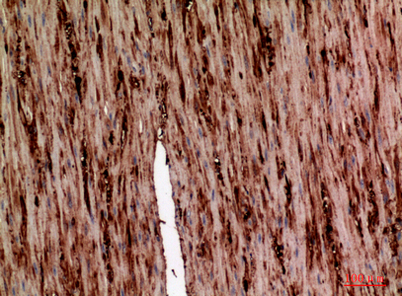

Product name: AAT rabbit pAb

Dilutions: Western Blot: 1/500 - 1/2000. IHC-p: 1:100-1:300. ELISA: 1/10000. Not yet tested in other applications.

Immunogen: The antiserum was produced against synthesized peptide derived from the N-terminal region of human SERPINA1. AA range:1-50